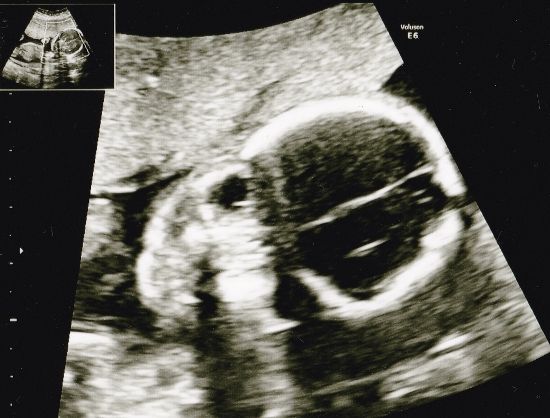

Ai niin, kuvakin meille toki annettiin matkaan. Sellainen, joka aiheuttaa itsessäni pientä hymyilyä, sillä se vahvistaa mielikuvaani siitä, että kätilöillä on tiukkoihin faktoihin keskittyviä lääkäreitä ehkä hiukan enemmän "näkemystä" näihin ehkä turhempiin, mutta perhettä kovasti ilahduttaviin asioihin:

Siinähän hän, suloinen, tässä potretissa ehkä enemmän hurjaa merirosvolippua muistuttava tyttäremme. ♥ Sopii toisaalta tähän samansuuntaisista teemoista nimeensä inspiraation saaneeseen blogiinkin, haha!